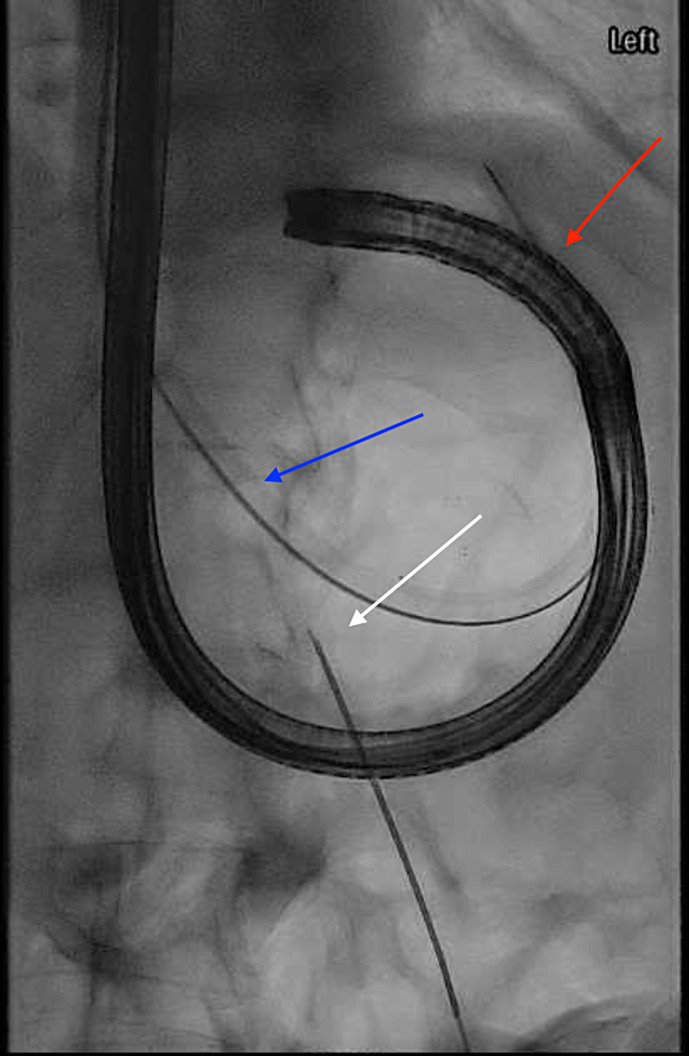

Introduction: We report the case of a 60-year-old female with a history of perforated gastric ulcer, abdominal abscesses, enterocutaneous fistula, and small bowel obstruction requiring durable gastric decompression prior to delayed fistula takedown. The patient had contraindications to or failed attempts at traditional gastrostomy approaches (surgical, endoscopic, interventional radiology).

Case report: Gastrostomy was successfully performed via a novel technique combining interventional radiology and endoscopic placement.